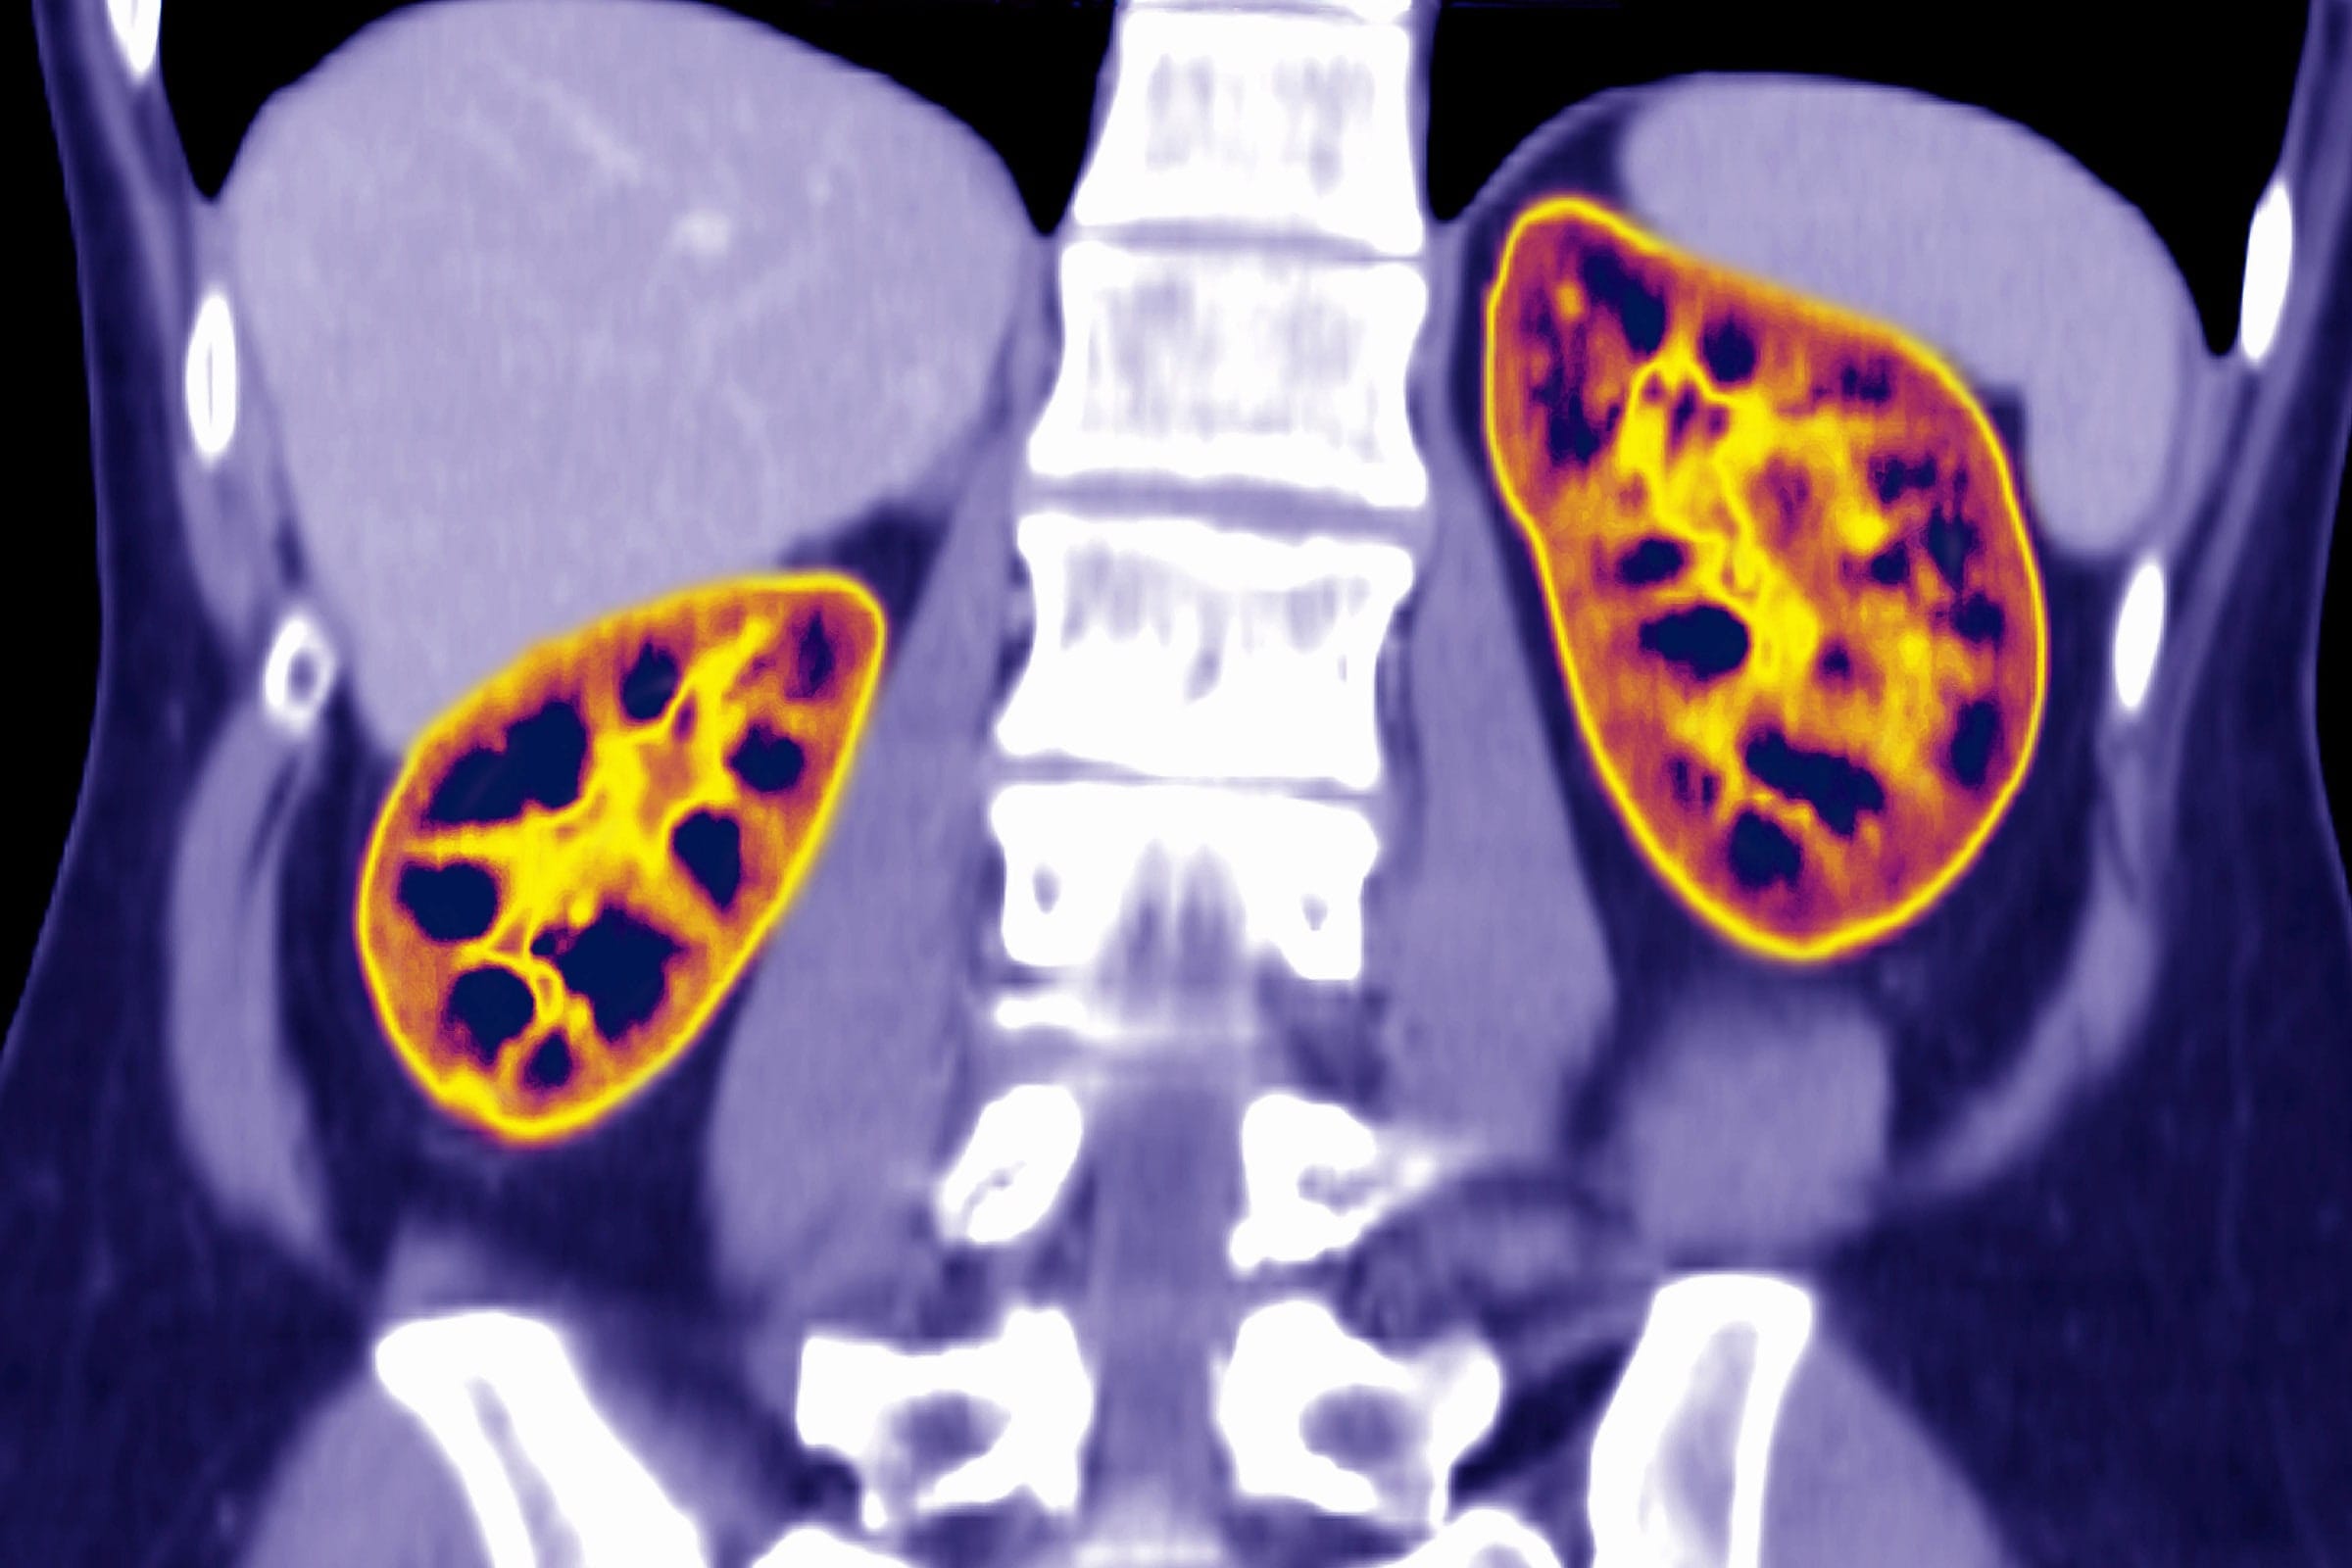

Hastaların böbrek hastalığının ciddiyetini anlamak için eGFR olarak bilinen bir değer kullanılıyor. Fotoğraf: James Cavallini/Science Source

Yeni çalışma, CKD-EPI adı verilen, kişilerin kan testindeki kreatinin atık ürün düzeyini, tahmini glomerül filtrasyon hızı (eGFR) adı verilen böbrek işlevi ölçütüne dönüştüren standart hesaplamayı inceledi. Düşük değerler daha kötü bir böbrek işlevi anlamına geliyor; değerler kişilerin hastalığının ciddiyetini kategorilendirmek ve aldıkları tedaviye yol göstermek için kullanılıyor. Denklem, kişinin yaşını ve cinsiyetini de hesaba katıyor. Siyah hastaların değerine ek bir %15,9 miktar ekleniyor.